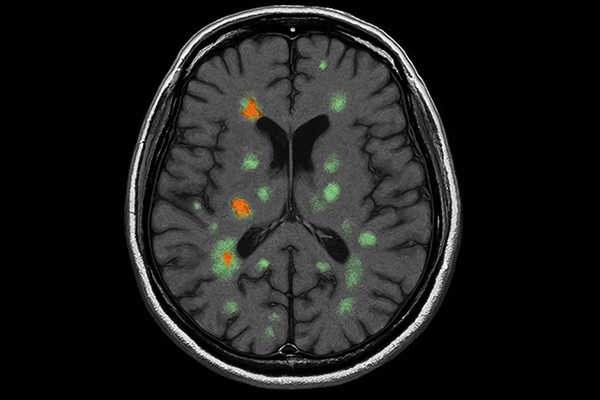

Imagistica prin rezonanță magnetică (RMN)

RMN-ul este o investigație esențială în diagnosticarea sclerozei multiple. Ajută la identificarea:

- Leziunilor caracteristice (plăci) la nivelul creierului și măduvei spinării

- Leziunilor active (cu contrast) și cronice

- Atrofiei cerebrale

Un RMN cerebral și medular oferă informații importante despre numărul leziunilor și activitatea bolii. Pentru a înțelege mai bine rolul acestei investigații, poți citi mai multe despre importanța RMN-ului în diagnosticarea diferitelor afecțiuni neurologice.